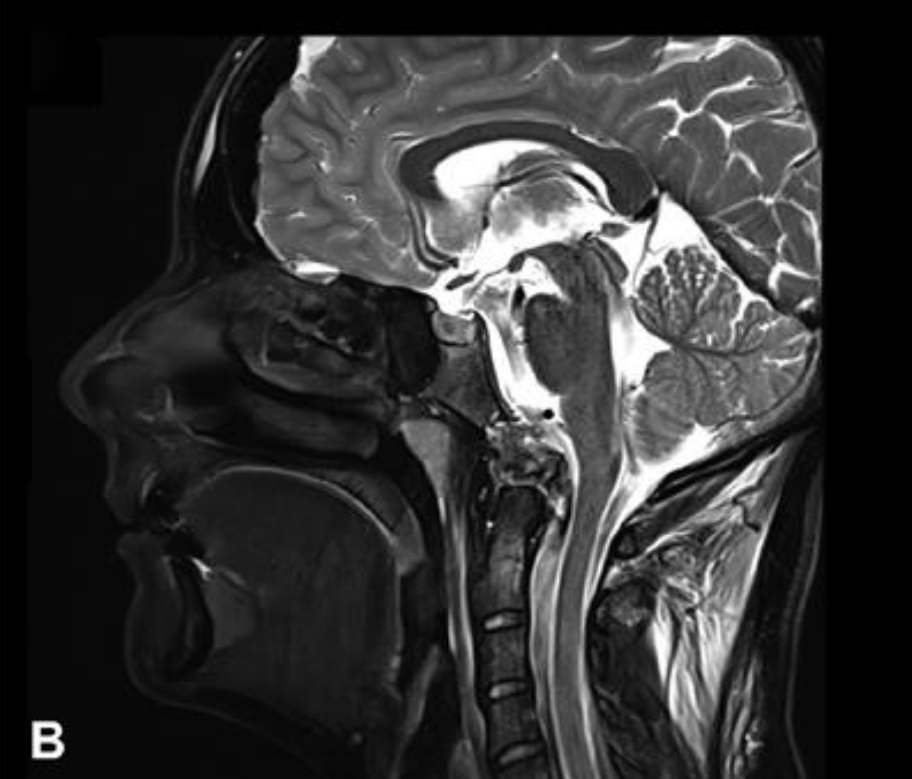

病例三:一位21岁女性患者,因颈部疼痛检查发现枕骨大孔和颅颈交界区存在脊索瘤,病变扩展至硬膜内。该脊索瘤患者还伴有明显的骨质破坏和硬膜内延伸表现。

病例三:21岁女性脊索瘤

年轻女性因颈部疼痛就诊,MRI发现颅颈交界区脊索瘤,伴骨质破坏和硬膜内延伸,累及双侧椎动脉。

治疗策略:采用内镜辅助的前外侧入路顺利切除肿瘤,术后几天行枕颈融合术确保稳定性。